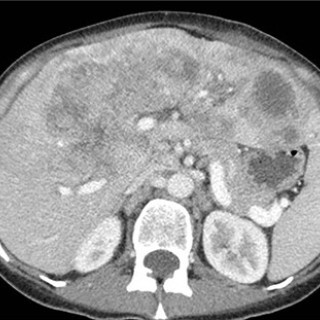

Bildet viser leukemiske hudinfiltrasjoner hos en mann i 50-årene diagnostisert med akutt myelogen leukemi. Pasienten ble overført fra lokalsykehus til hematologisk avdeling ved universitetssykehus, der han ble innlagt med spørsmål om alvorlig infeksjon. Han hadde da 14 dagers sykehistorie med tiltakende luftveissymptomer, økende dyspné og fallerende allmenntilstand. De siste fire dagene var det også tilkommet flere flekkvise, nodulære hudlesjoner, mest uttalt på hals, bryst og overekstremiteter. Blodprøver ved ankomst universitetssykehuset viste hemoglobin 8,1 g/dL (referanseområde 13,4–17,0)...